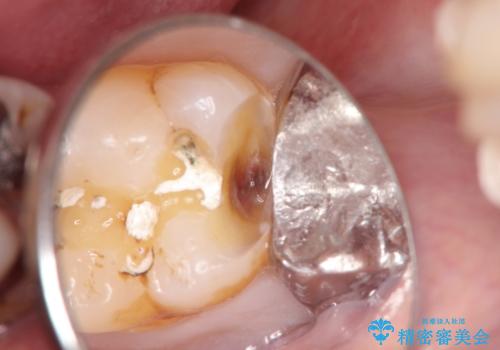

- 定期健診にてむし歯を認めたためゴールドインレーにて治療を行いました。

鼻炎により鼻で息ができず、のどに水をためないように配慮しながら治療を行いました。

休憩をはさみながら、患者様にも頑張っていただき2回で治療を終了できました。